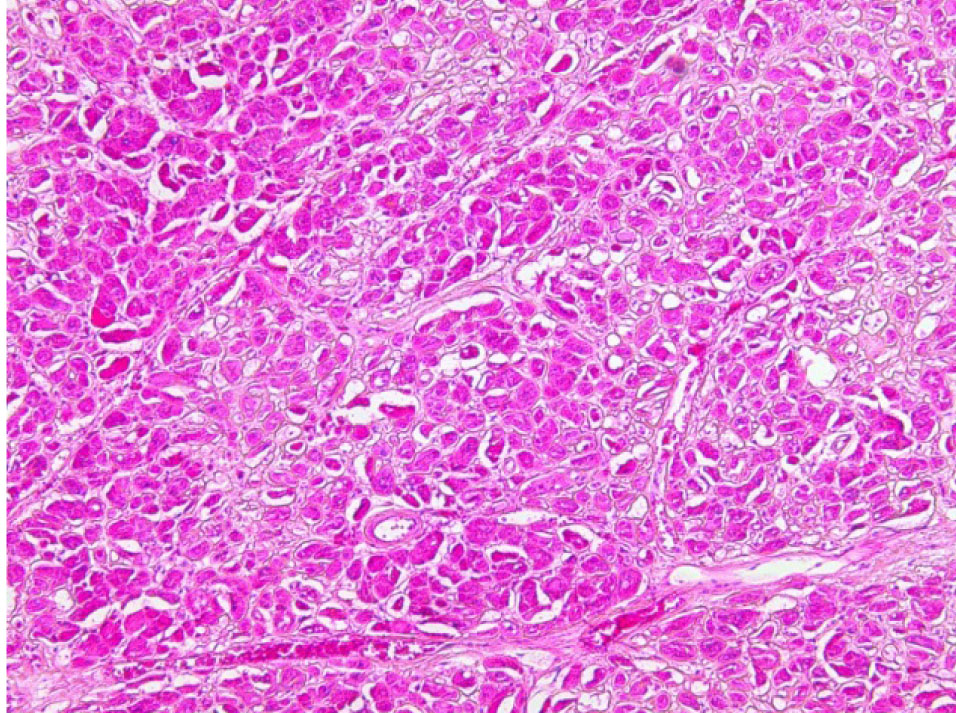

Почки – резкое уменьшение числа клубочков, отдельные полностью замещены однородной массой, дающей положительную реакцию на амилоид (рис. 3). В стенке сосудов также видны отложения амилоида (рис. 4).

Рис. 3. Почечный клубочек замещен амилоидными массами. Окраска конго красный, ×400

Рис. 4. Амилоид в стенке сосуда в почке. Окраска конго красный, ×200